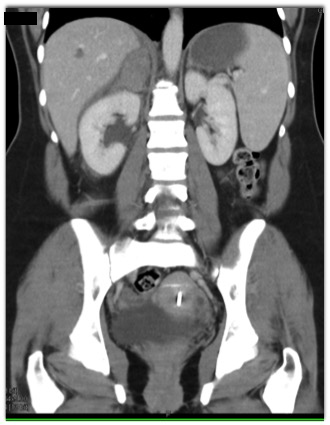

In this patient with right upper quadrant pain the most likely diagnosis is?

adrenal metastases

aldosteronoma

adrenal hemorrhage

acute hepatitis